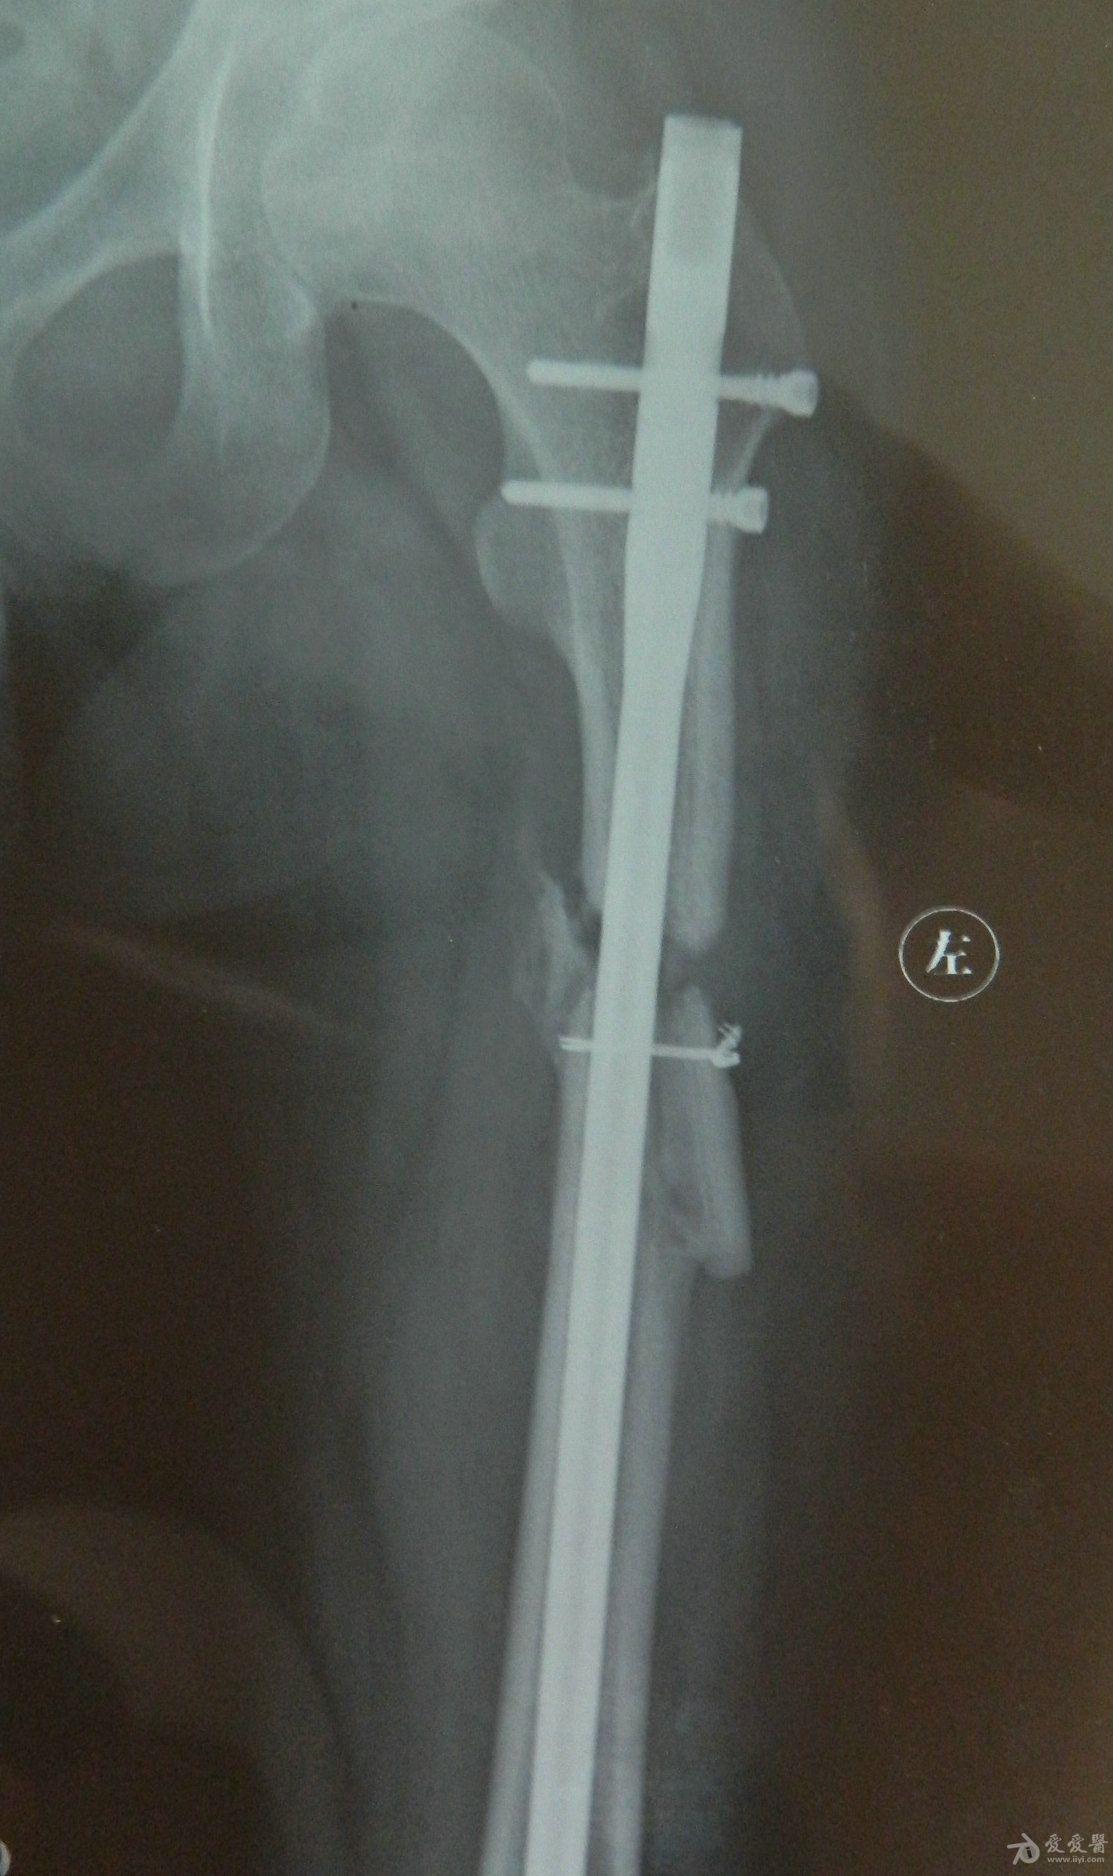

骨骨干骨折长好后图片,大腿骨干骨骨折恢复图

股骨干骨折

股骨干骨折术后骨不愈合附图

骨折经治疗 两月后拍片 请教医生恢复效果

大腿骨干骨骨折恢复图

股骨干骨折图片

大腿股骨骨折愈合图片

大腿骨折65天骨痂图

大腿骨折三个月骨痂图

大腿骨折两个月骨痂图

大腿骨折愈合标准图片